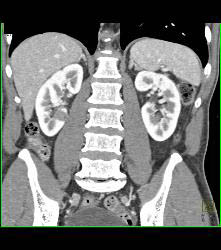

Gastric Adenocarcinoma With Celiac Nodes